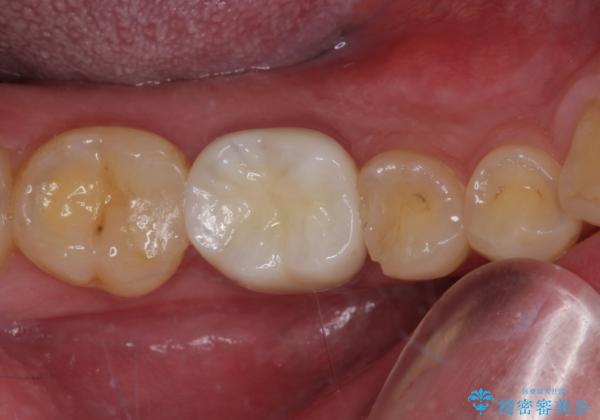

咬合力が強いため、強化セラミッククラウンでの補綴治療を行うこととしました。

強化セラミッククラウンは単一素材のため、非常に高強度でありますが色調は単調なものとなり、隣在歯と調和させることは困難です。